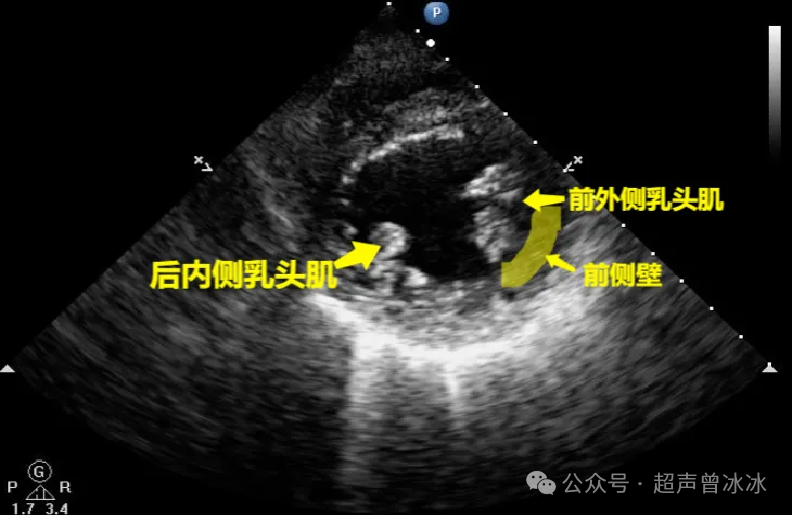

另外,我们需要注意的是--------有的小伙伴认为各回各家,各找各妈,前外侧乳头肌发出的腱索就支持二尖瓣前叶,后内侧乳头肌发出的腱索就支持二尖瓣后叶。

这种观点是错误的。

正确的应该是:

前外侧乳头肌发出的腱索支持二尖瓣前外侧联合、前叶和后叶的前外侧部位。后内侧乳头肌发出的腱索支持二尖瓣后内侧联合、前叶和后叶的后内侧部位。

绕晕了吧?直接看图就明了了:

11fce4dc97527ef84ce2b3775d0f605b0b3b4a95